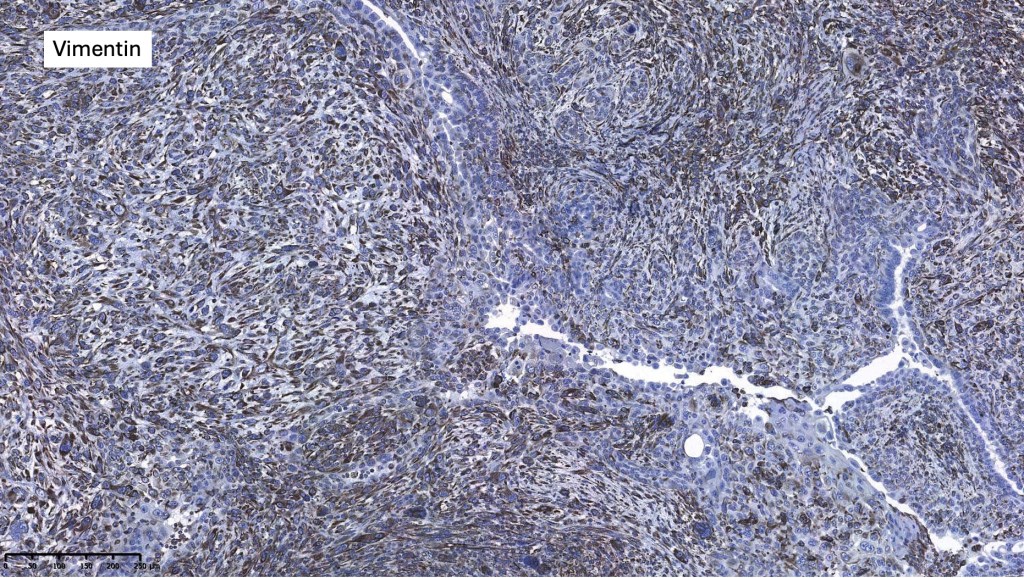

•CEA, EMA & CK7 +ve

.CK20, p63, TTF-1, PSA, ER, PR -ve